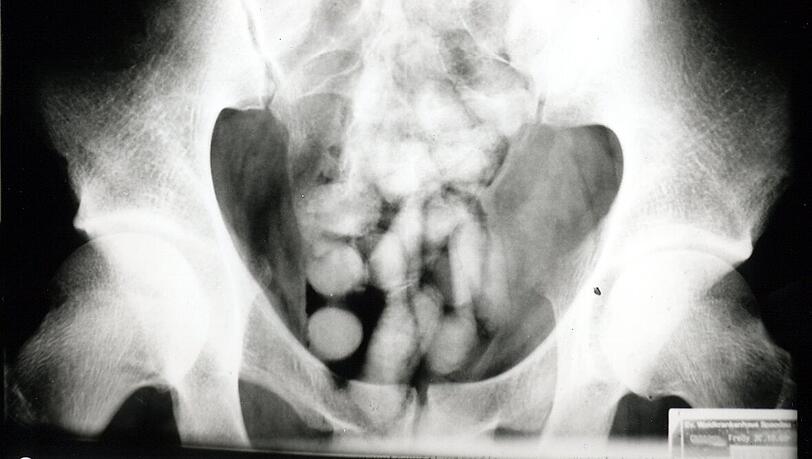

Ein Drogenwischtest fiel positiv aus und zeigte Kokain an. Da aber weder im Gepäck noch am Körper Drogen gefunden werden konnten, wurde der Mann zum Röntgen ins Krankenhaus gebracht. "Das Röntgenbild bestätigte den Verdacht der Zöllner. Im Laufe des Tages kamen 97 Behältnisse mit Kokain zum Vorschein, die über den natürlichen Weg ausgeschieden wurden", teilt die Pressesprecherin des Hauptzollamts München, Marie Müller, mit.